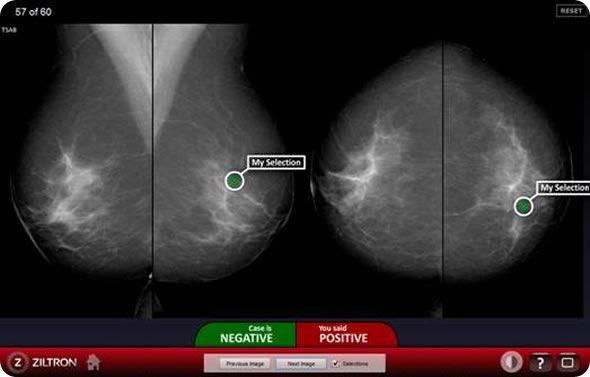

Figure 1

Figure 1. Screenshot of the BREAST assessment system. In this case the user diagnosed cancers in a normal case. In practice this may result in an unnecessary and expensive biopsy procedure and significant stress to the patient